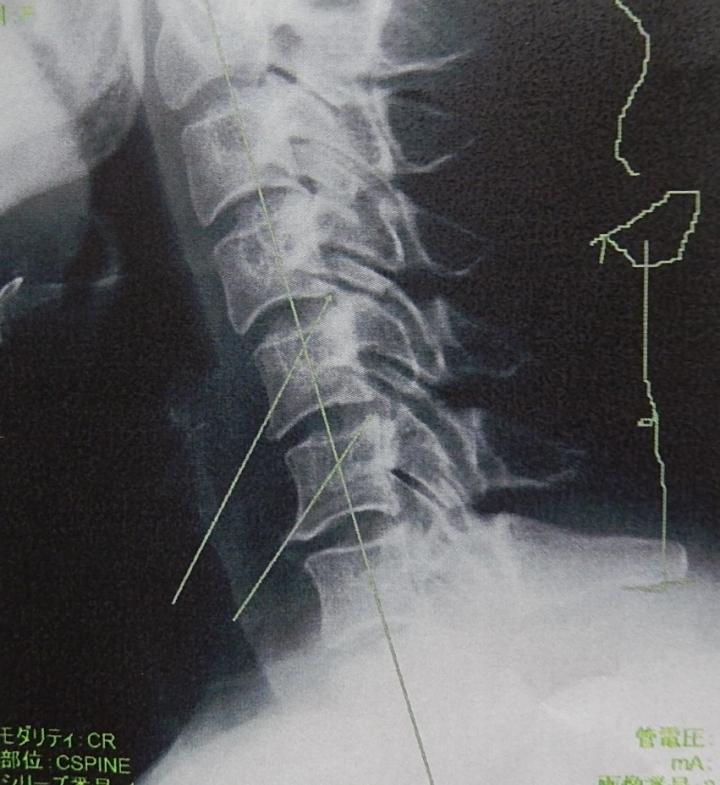

じゃじゃ~ん🎶 これ、管理人の首~~~~~(*'▽')

見事な「ストレートネック」!

重い頭を支えきれない首になってしも~た~!

首は曲がっていないといけないそうで、2本の矢印の先に負担がかかってしびれている~。